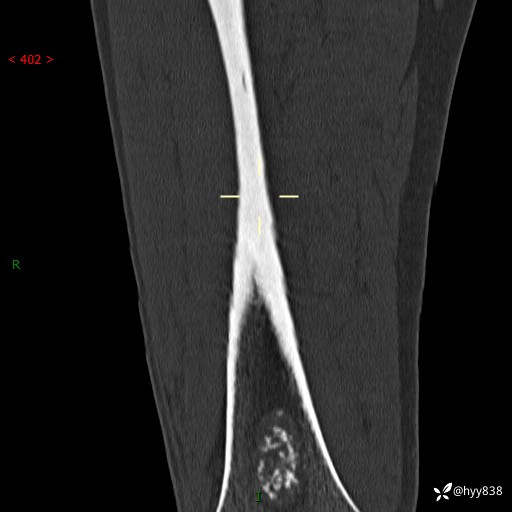

CT

img